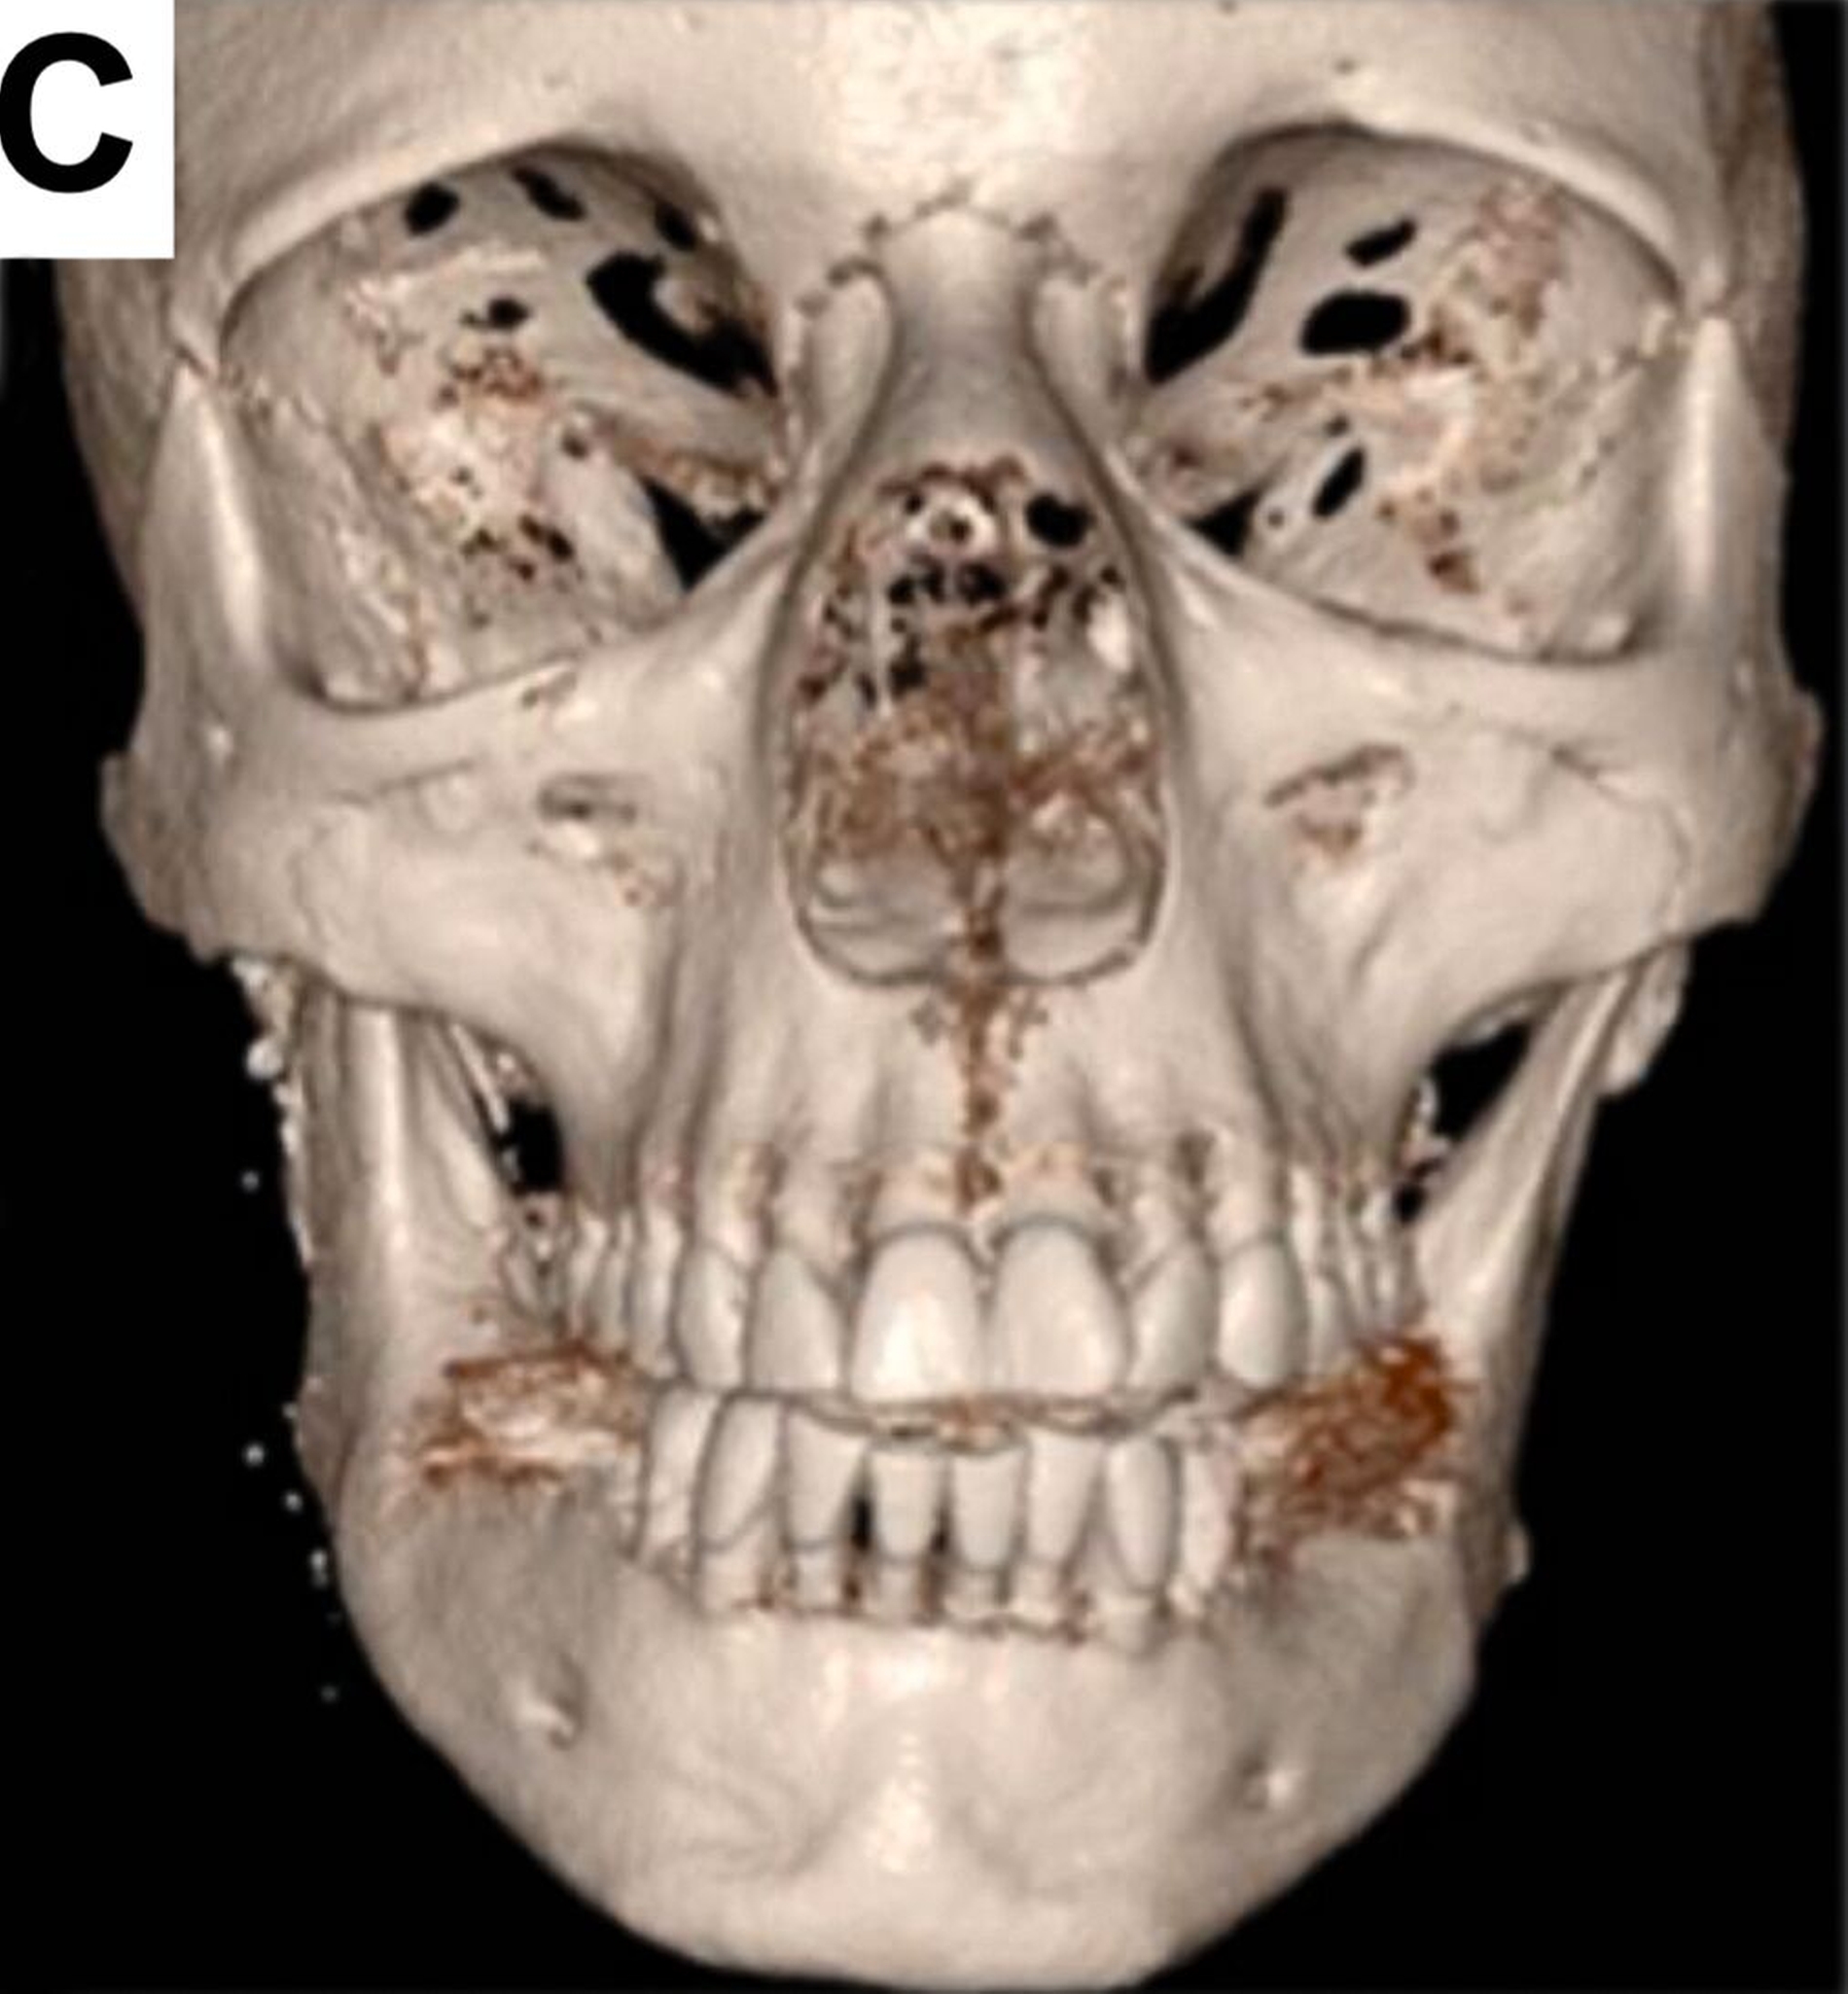

Bei der computertomografischen Untersuchung, die während der Patientenvorstellung durchgeführt wurde, wurde der totale Ersatz des rechten Kondylus durch die bereits beschriebene Endoprothese festgestellt, jedoch ohne Ersatz der Fossa mandibulae, was einem partiellen Kiefergelenkersatz entsprach. Das in situ befindliche Prothesenwerkstück hatte bereits zu einer nahezu vollständigen Erosion der mittleren Schädelbasis geführt (Abbildung 1).

Um eine weitere Dislokation nach intrakraniell zu vermeiden, erfolgte eine Woche nach der Erstvorstellung der Patientin die Entfernung des Endoprothesenwerkstücks (Abbildung 2).